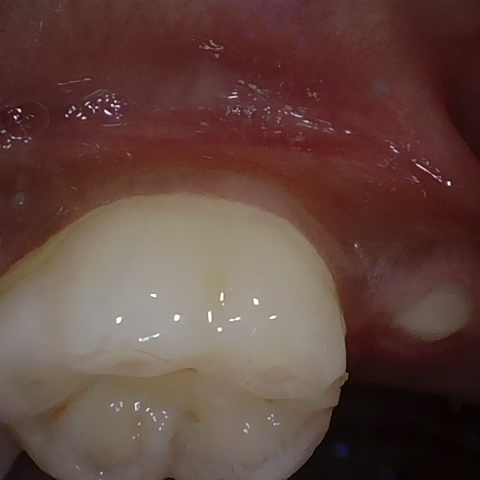

Annotated as "Good"